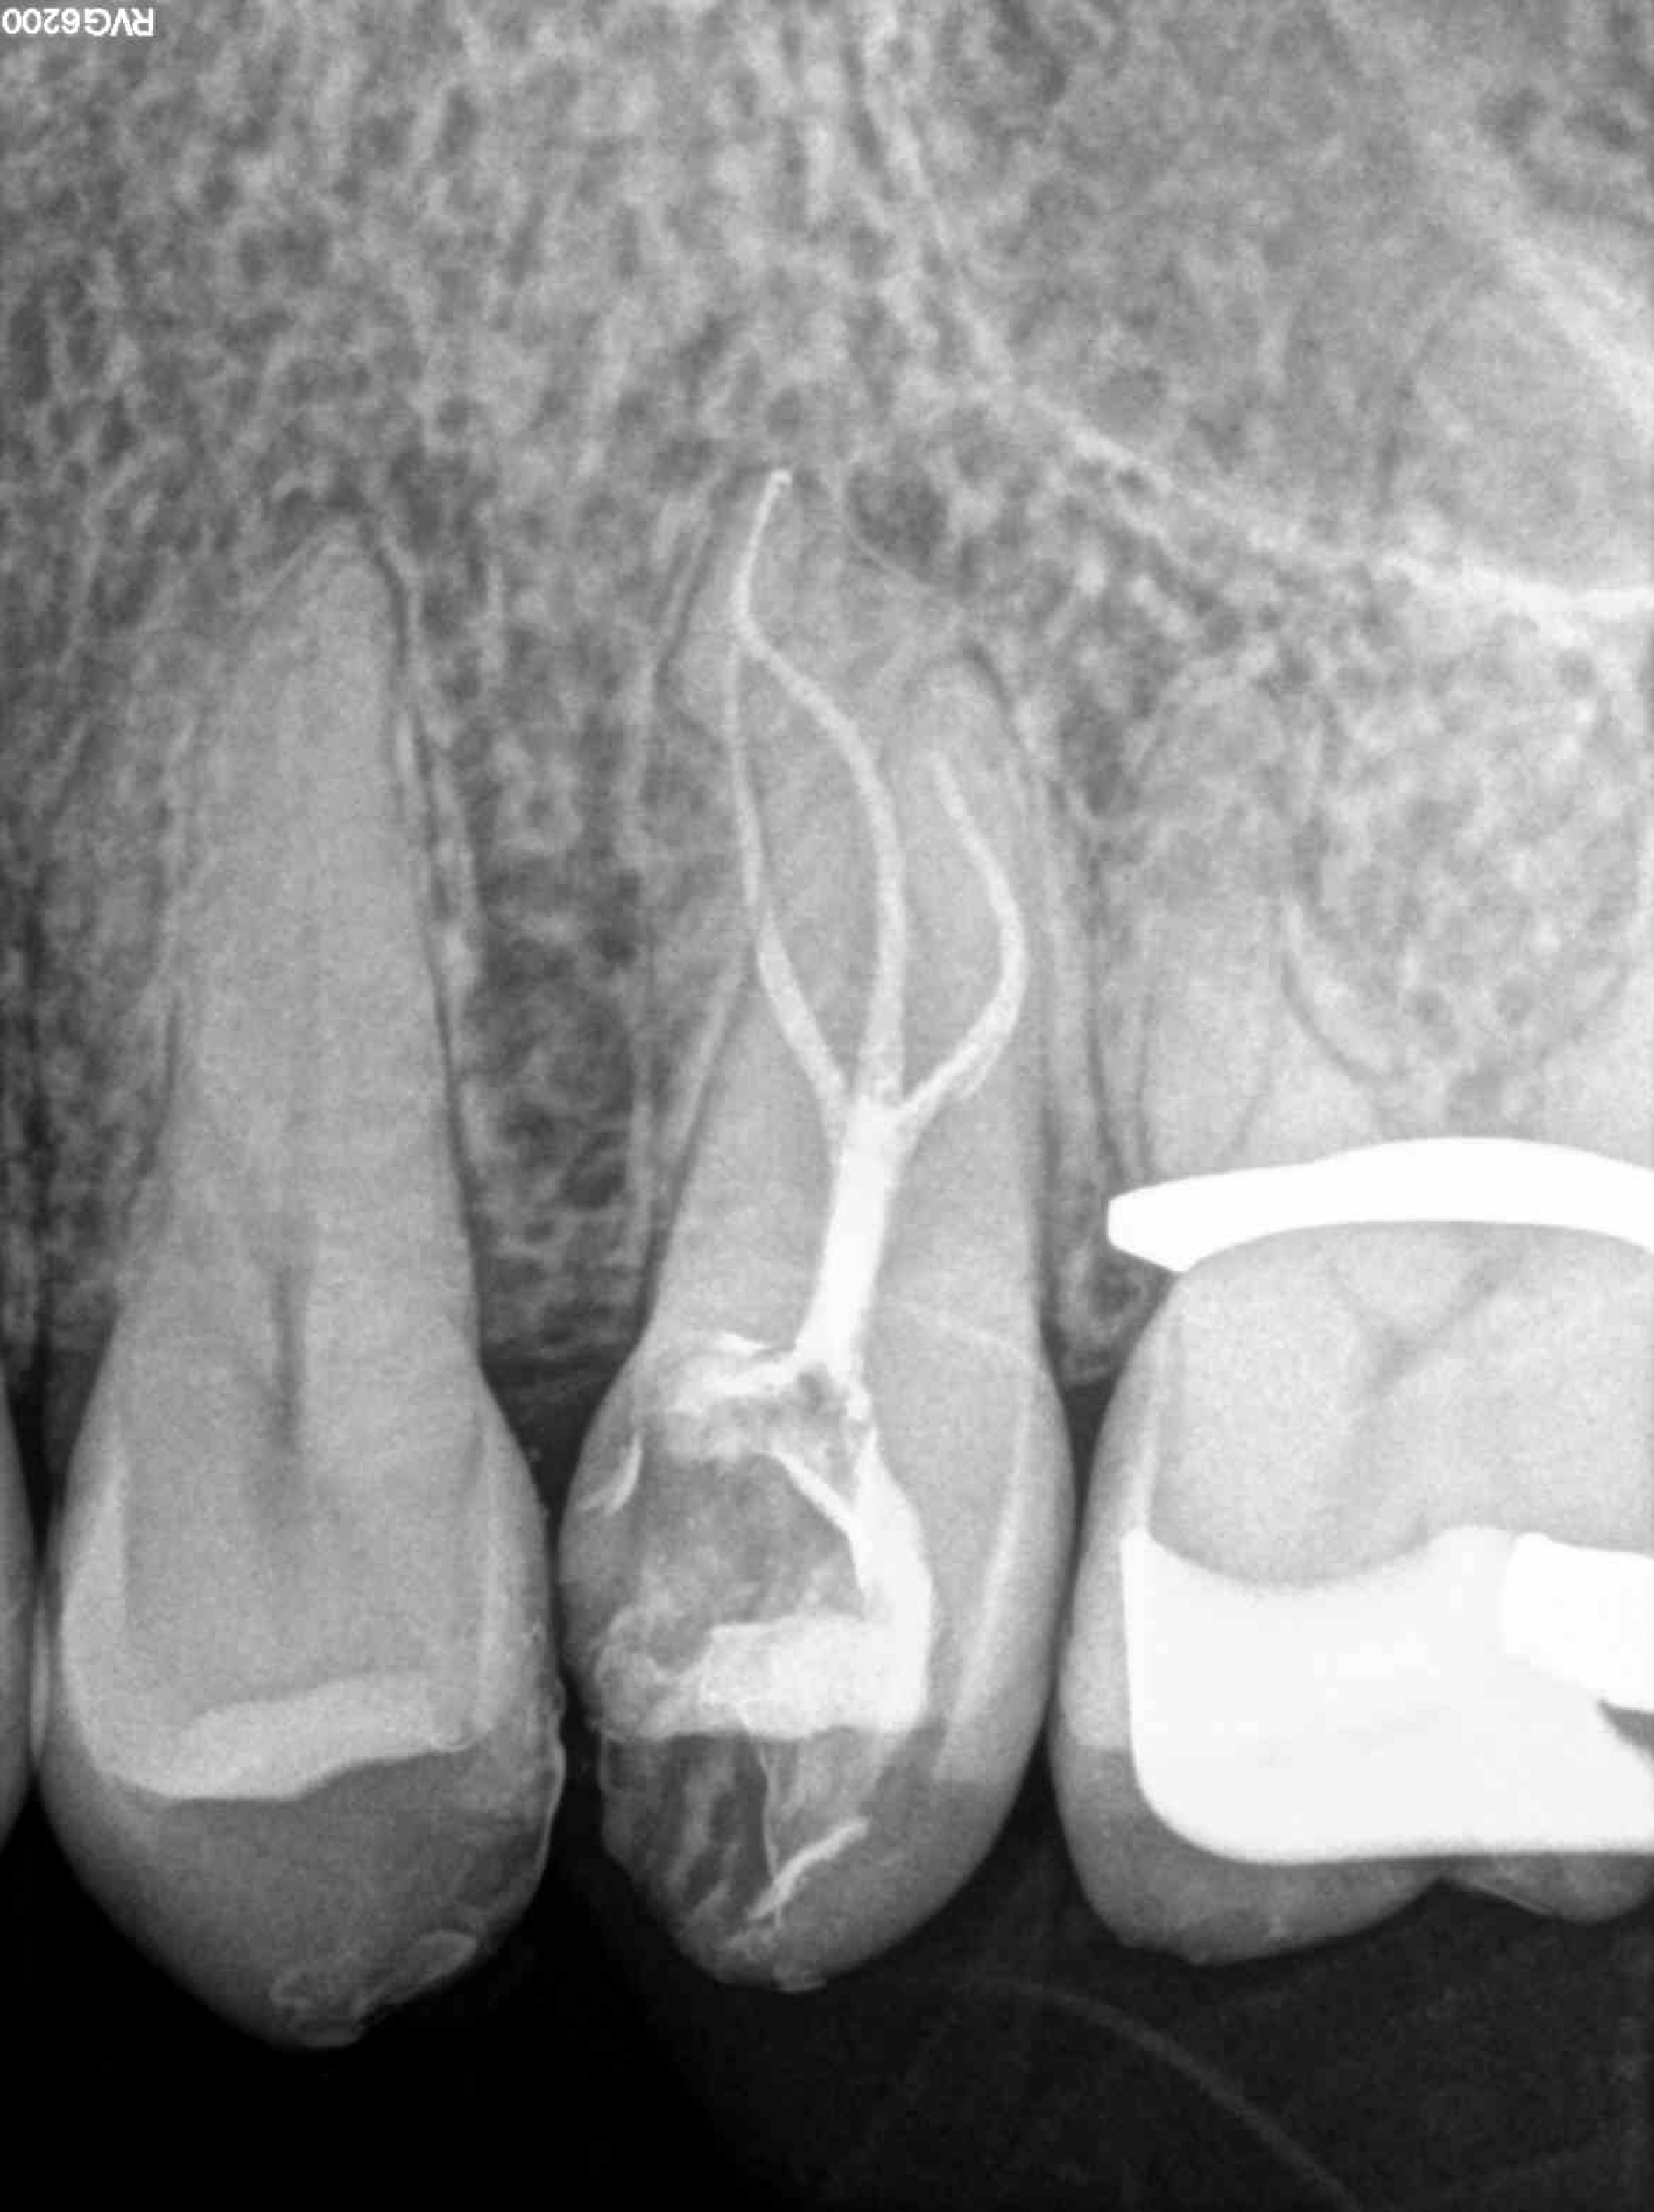

* Haz click sobre las radiografías para verlas a mayor tamaño

Haz click sobre las radiografías para verlas a mayor tamaño